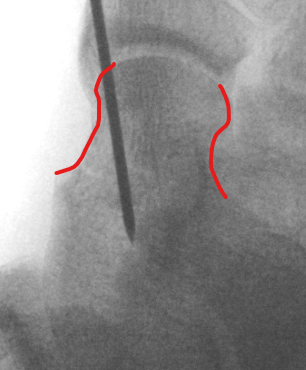

2. Reduction - avoid varus and shortening medial neck

- often medial comminution

Canale view

- evaluates talar neck

- foot everted 15 deg

- look for medial shortening / varus

AP, Canale and Lateral xray